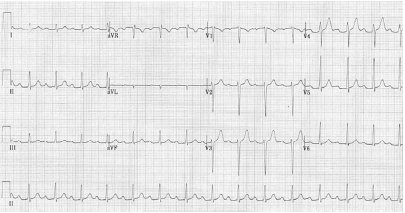

Um paciente de 69 anos de idade, com antecedentes de tabagismo, hipertensão arterial e diabetes, apresentava, havia três dias, episódios de precordialgia ao repouso, em queimação, de moderada intensidade, sem irradiação e com alívio espontâneo em menos de 20 minutos, que se tornaram mais frequentes e de maior intensidade álgica nas últimas 24 horas, período em que os episódios ocorreram três vezes. Na admissão, ele relatou persistência do desconforto torácico havia uma hora. Estava em uso regular de enalapril e metformina. No exame físico, encontrava-se eupneico, com pressão arterial de 148 mmHg × 74 mmHg, frequência cardíaca de 92 bpm e ritmo cardíaco regular, em dois tempos, sem sopros. O restante do exame físico foi normal. A dosagem da troponina ultrassensível foi normal. O paciente foi submetido ao exame de eletrocardiograma (com calibração padrão), que evidenciou o seguinte resultado.

Considerando esse caso clínico hipotético e as Diretrizes da Sociedade Brasileira de Cardiologia de 2021, julgue o item seguinte.

Recomenda-se o uso de metoprolol por via oral.

Um paciente de 69 anos de idade, com antecedentes de tabagismo, hipertensão arterial e diabetes, apresentava, havia três dias, episódios de precordialgia ao repouso, em queimação, de moderada intensidade, sem irradiação e com alívio espontâneo em menos de 20 minutos, que se tornaram mais frequentes e de maior intensidade álgica nas últimas 24 horas, período em que os episódios ocorreram três vezes. Na admissão, ele relatou persistência do desconforto torácico havia uma hora. Estava em uso regular de enalapril e metformina. No exame físico, encontrava-se eupneico, com pressão arterial de 148 mmHg × 74 mmHg, frequência cardíaca de 92 bpm e ritmo cardíaco regular, em dois tempos, sem sopros. O restante do exame físico foi normal. A dosagem da troponina ultrassensível foi normal. O paciente foi submetido ao exame de eletrocardiograma (com calibração padrão), que evidenciou o seguinte resultado.

Considerando esse caso clínico hipotético e as Diretrizes da Sociedade Brasileira de Cardiologia de 2021, julgue o item seguinte.

O paciente deverá realizar o teste ergométrico em regime ambulatorial, para avaliação diagnóstica e prognóstica.

Um paciente de 69 anos de idade, com antecedentes de tabagismo, hipertensão arterial e diabetes, apresentava, havia três dias, episódios de precordialgia ao repouso, em queimação, de moderada intensidade, sem irradiação e com alívio espontâneo em menos de 20 minutos, que se tornaram mais frequentes e de maior intensidade álgica nas últimas 24 horas, período em que os episódios ocorreram três vezes. Na admissão, ele relatou persistência do desconforto torácico havia uma hora. Estava em uso regular de enalapril e metformina. No exame físico, encontrava-se eupneico, com pressão arterial de 148 mmHg × 74 mmHg, frequência cardíaca de 92 bpm e ritmo cardíaco regular, em dois tempos, sem sopros. O restante do exame físico foi normal. A dosagem da troponina ultrassensível foi normal. O paciente foi submetido ao exame de eletrocardiograma (com calibração padrão), que evidenciou o seguinte resultado.

Considerando esse caso clínico hipotético e as Diretrizes da Sociedade Brasileira de Cardiologia de 2021, julgue o item seguinte.

A CK-MB massa deve ser dosada para confirmação diagnóstica.